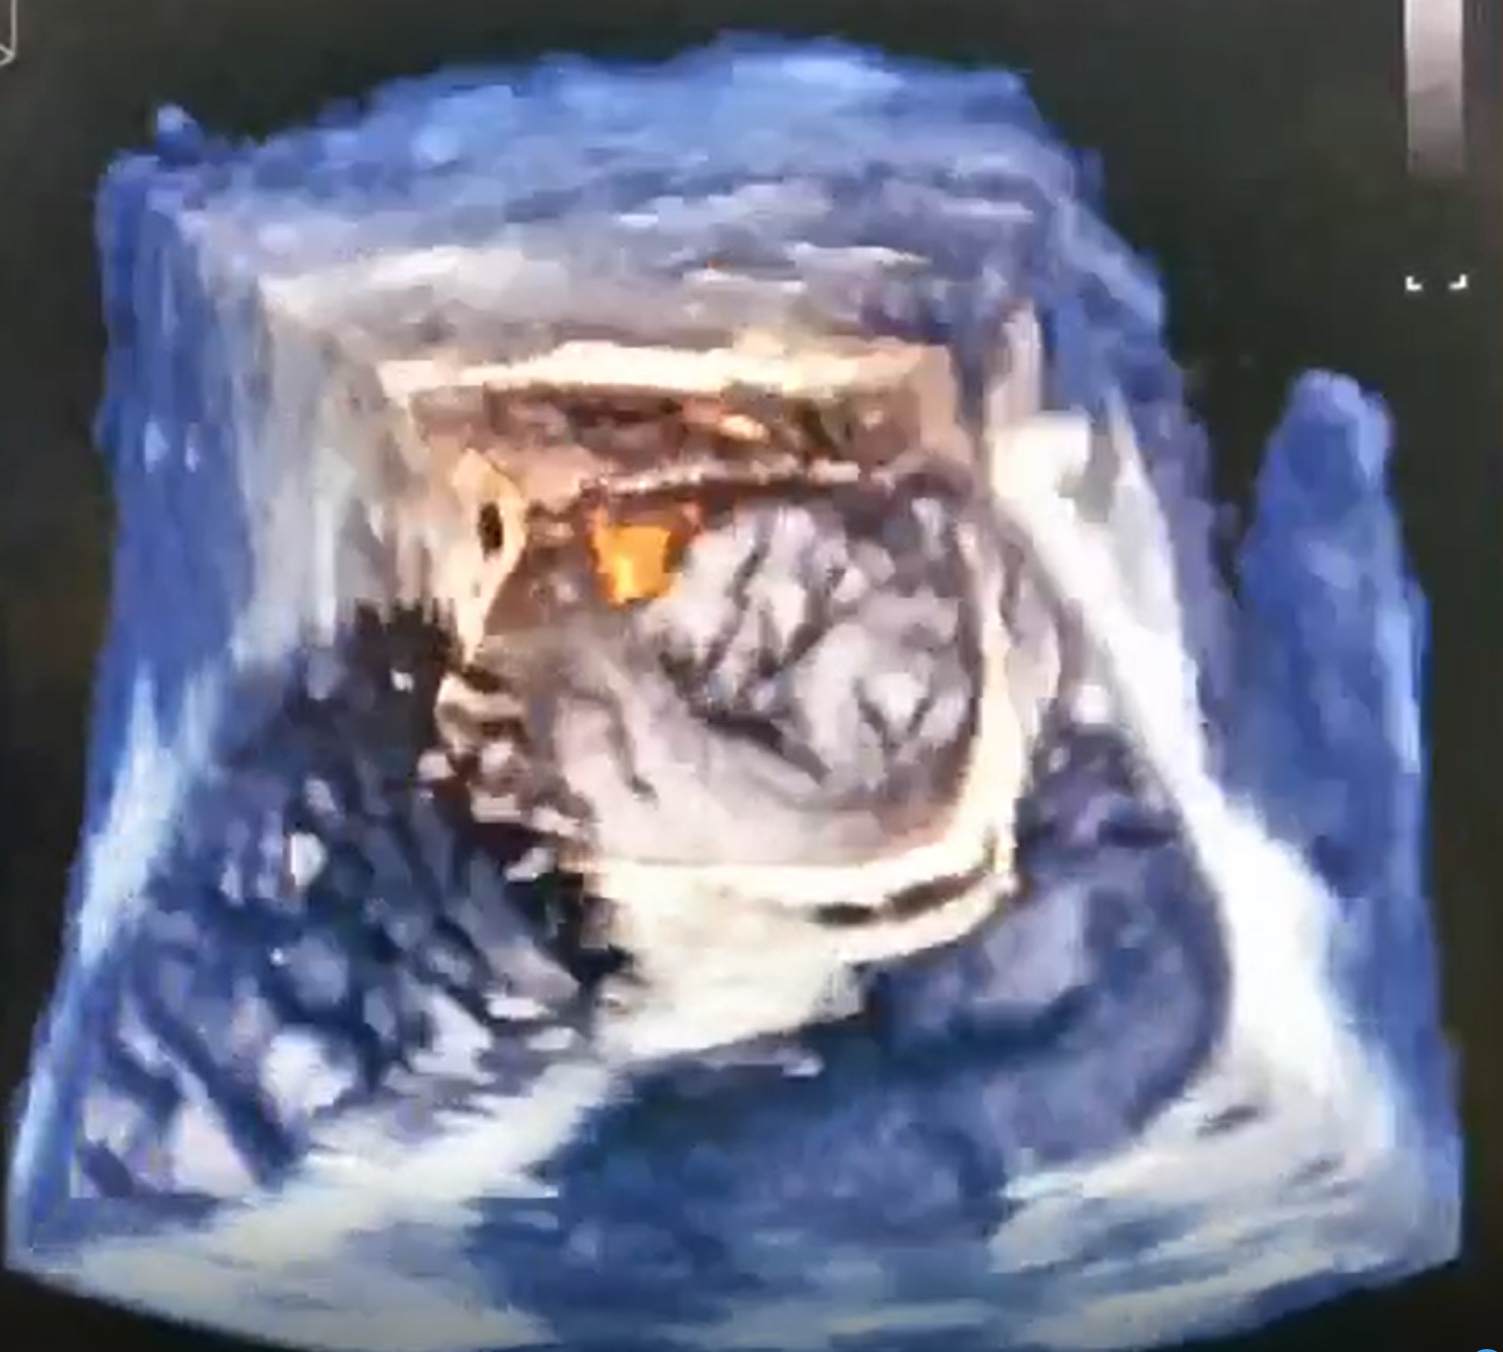

患者为66岁男性,永久性房颤5年余。既往有脑卒中史,高血压病史。间断口服华法林治疗,期间有多个器官及部位出血。入院房颤相关评分:CHA2DS2-VASc评分5分,HAS-BLED出血评分4分。经科室讨论行左心耳封堵术以减低脑卒中和出血风险。术中造影见巨大开口“菜花状”左心耳,经仔细分析病例特点为巨大开口(直径为37mm),且有两个较大的分叶。无法用最大型号WATCHMAN 封堵器(直径为33mm)封堵成功。遂改变封堵策略,选择使用两枚封堵伞,植入两个分叶分别进行封堵,即左心耳封堵的Kissing封堵技术。术中选用两枚封堵器(直径为24mm)送入两个分叶,进行Kissing封堵,封堵效果很完美。